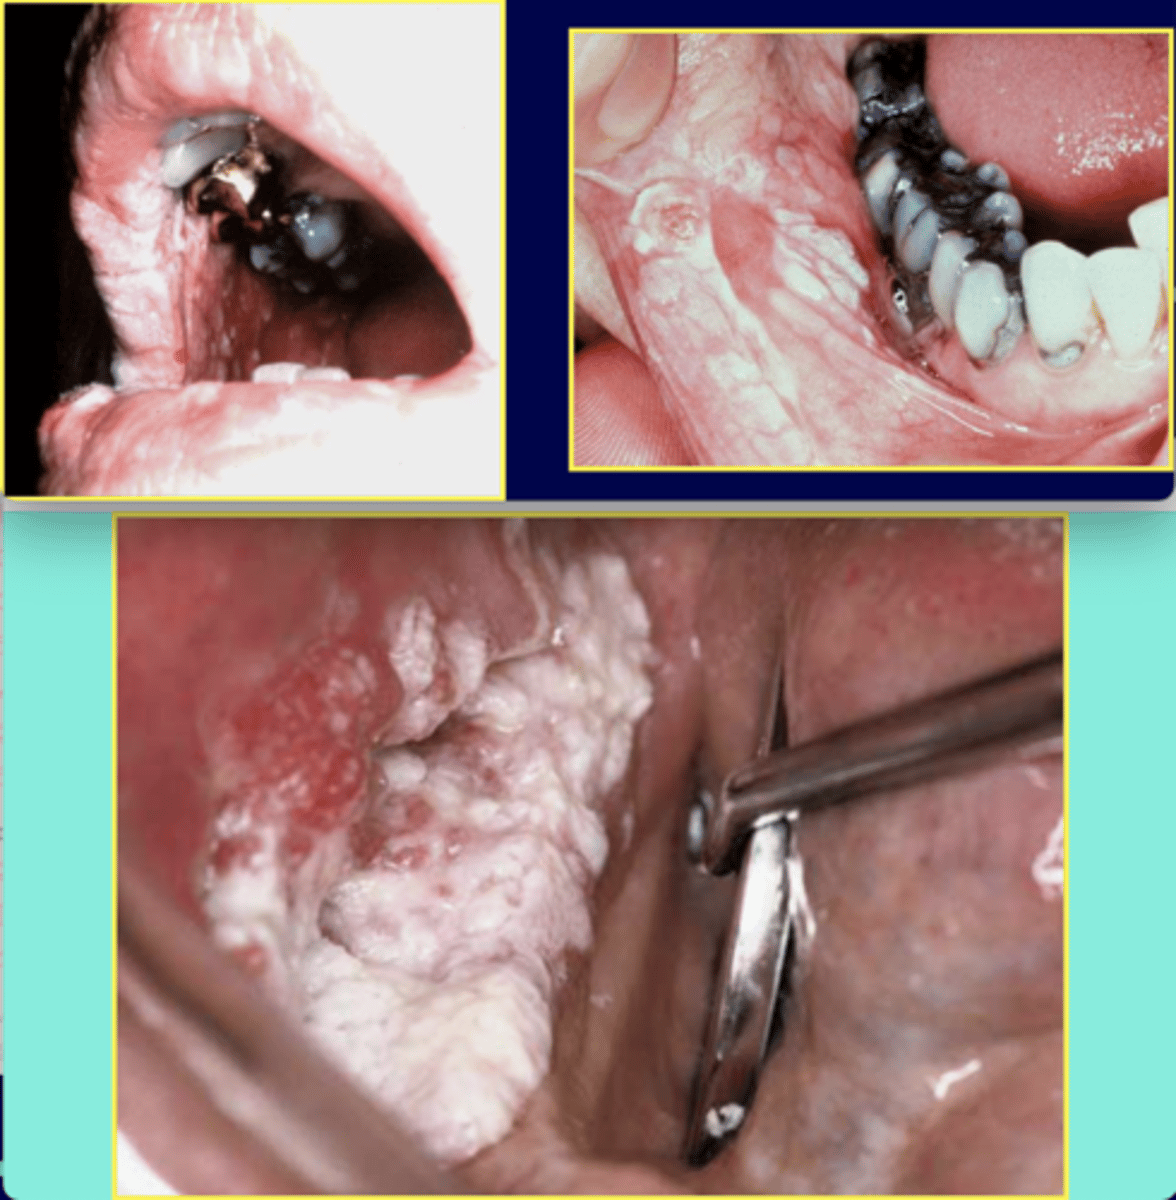

What is proliferative verrucous leukoplakia? (+ % malignant transformation, population)

⢠extensive, multiple white corrugated plaques

⢠NOT associated with risk factors -- 70% malignant change

⢠must biopsy

⢠Population: females over 50

What is verrucous carcinoma? (+ location, population, assoc. with)

diffuse white (or mixed) pebbly plaque

⢠common location: vestibule

⢠population: males over 65

⢠associated with smokeless tobacco

⢠slow growth